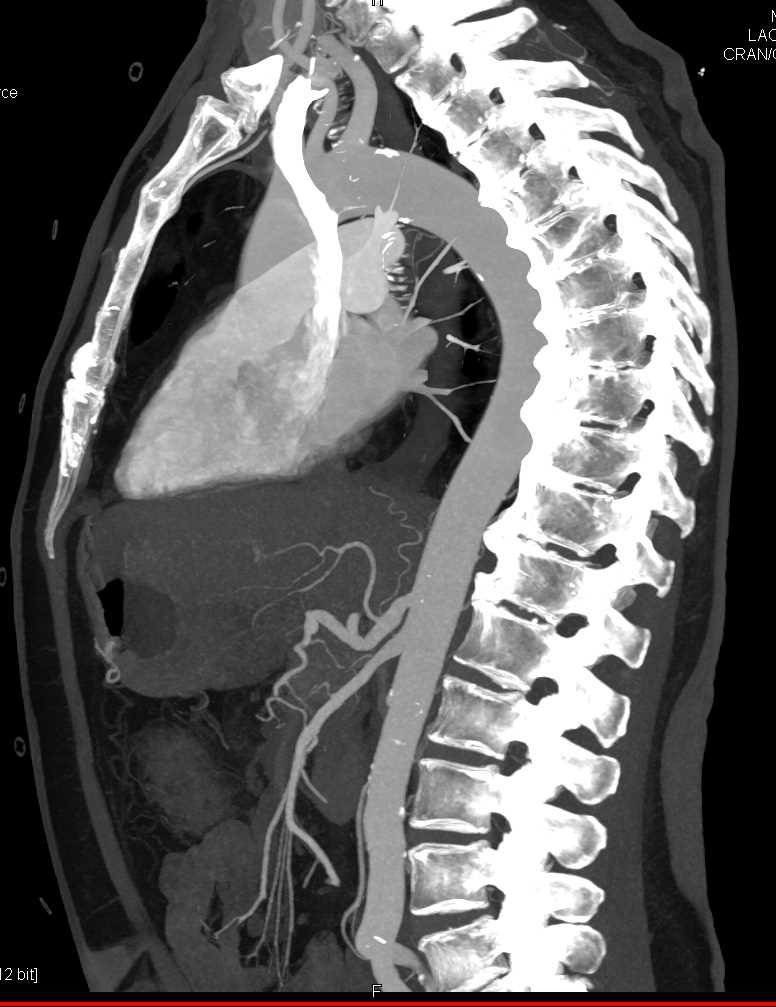

Carcinoma Head of Pancreas